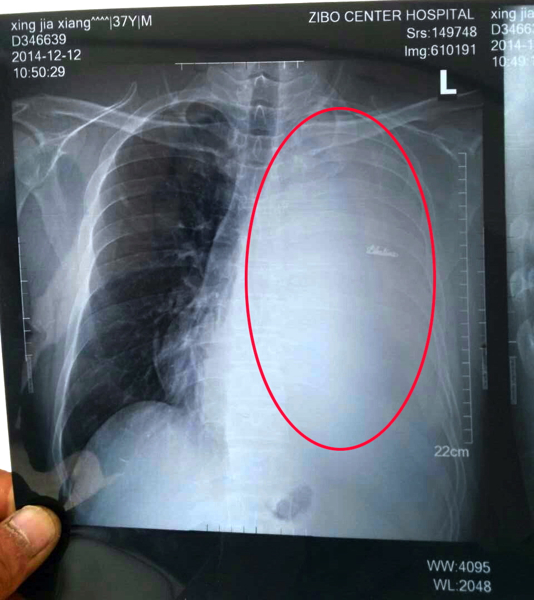

2014年12月12日检查结果显示左肺被积液淹没

2012年12月16日左肺抽调一半积液,肿瘤浮现

2014年12月17日肿瘤在CT上的显现(被圈部分)

2014年12月17日CT结果是肿瘤大小7.1*3.5cm